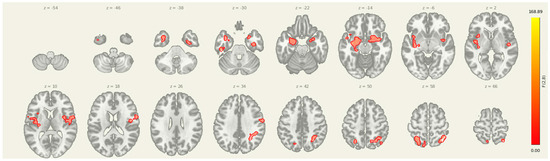

3.3. Amygdala Seed Pre > Post

Following the intervention, seed-to-voxel analysis revealed significantly greater amygdala connectivity at the pre-intervention timepoint compared to post-intervention in two clusters (Figure 3 and Table 4). The first was located in the left postcentral gyrus and somatosensory association area (MNI: +06, −38, +34; cluster size = 382 voxels; p-FDR = 0.0107), and the second was centered in the right superior frontal gyrus (MNI: +22, +22, +54; cluster size = 315 voxels; p-FDR = 0.0171). These results suggest a reduction in amygdala coupling with both sensorimotor and prefrontal regions after the combined rTMS and exercise intervention, consistent with decreased engagement of limbic-driven pain and vigilance networks.

Figure 3.

Seed-to-voxel connectivity reductions from the amygdala following intervention. Significant clusters reflect greater connectivity at pre-intervention compared to post-intervention (Pre > Post), including regions in the left postcentral gyrus and right superior frontal gyrus. Results are thresholded at p-FDR < 0.05 and shown in MNI space.

3.4. Insula Seed PRE > POST

For the insula seed, pre-intervention connectivity was significantly greater than post-intervention in multiple regions (Table 5): the left inferior frontal gyrus (MNI: −48, +12, −02; cluster size = 266 voxels; p-FDR < 0.001), the right inferior frontal gyrus (+48, +10, +00; 256 voxels; p-FDR < 0.001), and the left ventral striatum/putamen (−28, +02, +08; 65 voxels; p-FDR < 0.001). These regions are commonly involved in emotional processing, interoceptive integration, and motor preparation, and the observed reductions in connectivity suggest decreased insula-driven engagement of salience and affective-motor circuits following the intervention.

3.5. Amygdala-Insula-Thalamus Seed

Seeding from amygdala-insula-thalamus (Figure 4 and Table 6) revealed a significant post-intervention reduction in connectivity from the insula, amygdala, and thalamus to a cluster in the right superior frontal cortex (MNI coordinates: +20, +18, +56; cluster size = 133 voxels; p-FDR = 0.0065). These results suggest that improved prefrontal oversight may be a key mechanism through which the intervention alters pain-related brain dynamics in individuals with post-stroke headache.

Figure 4.

Post-intervention reductions in connectivity from limbic seed regions. Significant decreases in seed-to-voxel connectivity were observed from the amygdala, insula, and thalamus following the intervention. Clusters included sensorimotor, frontal, and subcortical regions. Results are thresholded at p-FDR < 0.05.